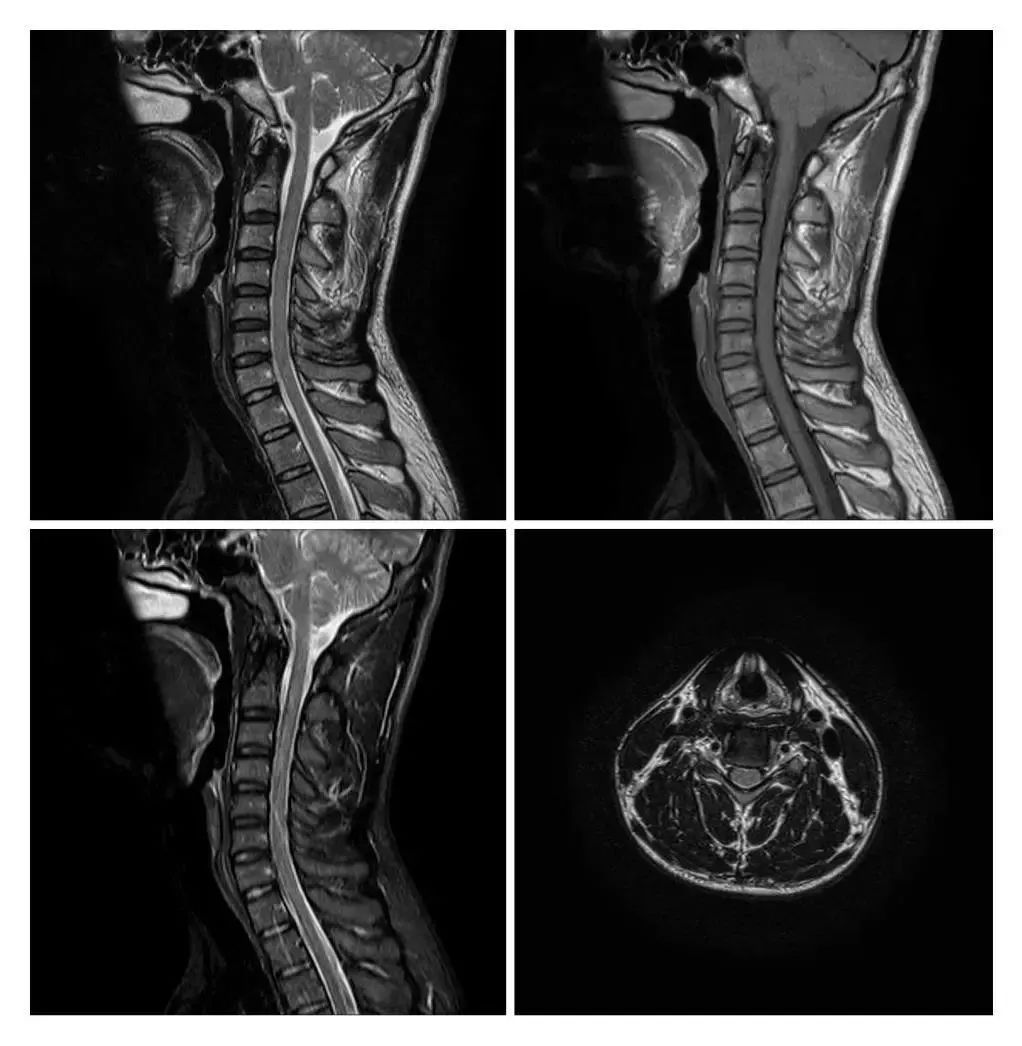

MRI現(xiàn)已應(yīng)用于全身各系統(tǒng)的成像診斷。效果最佳的是顱腦,及其脊髓、心臟大血管、關(guān)節(jié)骨骼、軟組織及盆腔等。而且不同于已有的成像術(shù),它對疾病的診斷具有很大的潛在優(yōu)越性。多序列成像、多種圖像類型,為明確病變性質(zhì)提供更豐富的影像信息,能很好的滿足臨床的診斷需求。

滑動查看更多